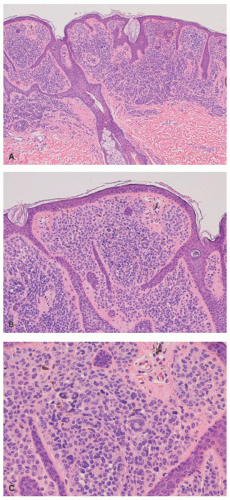

ATYPICAL MELANOCYTIC NEVUS

Atypical melanocytic nevus is a generic category based in part upon the clinical appearance and the pathologic features of the nevocellular proliferation. An irregular distribution of junctional nests, lentiginous (single-cell) junctional pattern, and nuclear alterations such as enlargement, density and coarseness of the chromatin, prominence of the nucleoli and mitotic figures, and their location are some of the qualifying histologic features of an “atypical nevus.” In a sense, it does not imply a specific subtype of nevus because these findings occur across the broad spectrum of lesions. Less than 10% of atypical nevi are diagnosed in the first two decades of life in one epidemiologic study.32 The most common context of an atypical melanocytic nevus in our experience is the so-called dysplastic or architecturally disordered nevus whose basic morphologic features include the following: (1) architecture with bridging of rete ridges; (2) nested nevus cells at the tips of the rete and single or lentiginous cells along the rete ridges; (3) continuous lamellar pattern of fibroplasia outlining the superficial papillary dermis; and (4) a shoulder of junctional nevus cells without an underlying

dermal component (Figure 22-9).33 The preference of one of us (LPD) is “melanocytic nevus with architectural disorder,” rather than dysplastic or Clark’s nevus. Despite the efforts of several convened consensus conferences, there is still a lack of consensus on many aspects of these lesions including the grading of atypia, its significance, and management.34,35,36,37,38 Socalled dysplastic features are not confined to the common AMN, but are seen in other nevocellular lesions such as the SN and combined nevus.39,40,41

FIGURE 22-9. Compound melanocytic nevus with architectural disorder (dysplastic nevus) in a 14-year-old male. Note the irregular junctional nests and bridging of rete ridges focally. Nuclear atypia is evident in the junctional melanocytes, with maturation in the dermal nests with smaller nevus cells.